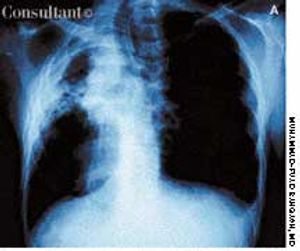

A 41-year-old man with a past history of tuberculosis presented to the emergency department with massive hemoptysis. The patient denied fever or chills but reported a 20-lb weight loss and intermittent hemoptysis during the last 6 months. Six years ago, he had been treated for tuberculosis.